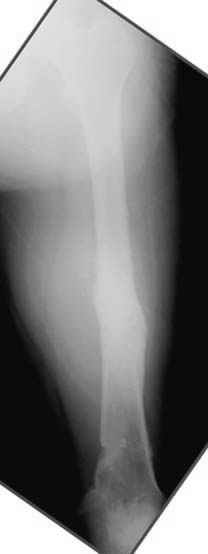

Несколько снимков из моей коллекции, чтобы разьяснить, почему мы до сих пор делаем различные варианты остеотомии.

На рисунке N1 предоперационный план лечения ложного сустава шейки бедра- линия ложного сустава, угол и направление введения импланта, клиновидная остеотомия в градусах и миллиметрах, второй снимок после коррекции, расчет, на сколько удлиняется конечность и размеры импланта;

N3 рисунок окончательный снимок, после операции моя рентгенограмма должен выглядеть примерно как эта картина. На N4 снимке клин перед удалением; N5 послеоперации 3 нед.; N6 окончательная рентгенограмма.

(доложен в Ст. Петербурге 2003 и в Москве 2004)

хотя даже если бы и инфекция , то nail exchange с рассверливанием канала - вариант дебрайдмента) Я думаю, что последовательность развития событий:

Узкий к-м канал - тонкий гвоздь- усталостный перелом дистальных винтов - развитие нестабильности и как ее результат остеолиз вокруг гвоздя - деформация анатомической оси бедра. Похоже, что я понял почему аппарат, а не новый гвоздь:-)